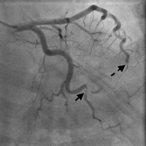

Effort thrombosis of the subclavian artery as a consequence of a unique anomaly

Evan R Brownie and Robert W Thompson

Journal of Surgical Case Reports, Volume 2018, Issue 4, April 2018, rjy072, https://doi.org/10.1093/jscr/rjy072